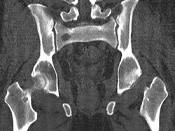

问题 男,46岁,双髋关节疼痛,反复感染,贫血,实验室检查血钙升高,本周蛋白尿(+),结合图像,最可能的诊断是()

选项 A.骨髓瘤 B.骨质疏松 C.骨转移瘤 D.骨囊肿 E.动脉瘤样骨囊肿

答案 A